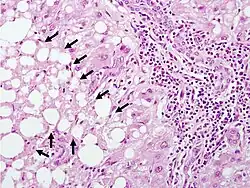

The second phase occurs between 24 hours and 72 hours following overdose and consists of signs of increasing liver damage. In general, damage occurs in liver cells as they metabolize the paracetamol. Hallmark pathology on liver biopsy includes regions of coagulative necrosis in zone 3 of the liver acinus, around the central venules, as these hepatocytes have higher concentrations of cytochrome P450 enzymes compared to zone 1 hepatocytes surrounding the portal venule of the acinus. Remaining viable hepatocyes frequently show ballooning injury and steatosis. [13] The individual may experience right upper quadrant abdominal pain. The increasing liver damage also changes biochemical markers of liver function; International normalized ratio (INR) and the liver transaminases ALT and AST rise to abnormal levels.[14] Acute kidney failure may also occur during this phase, typically caused by either hepatorenal syndrome or multiple organ dysfunction syndrome. In some cases, acute kidney failure may be the primary clinical manifestation of toxicity. In these cases, it has been suggested that the toxic metabolite is produced more in the kidneys than in the liver.[15]